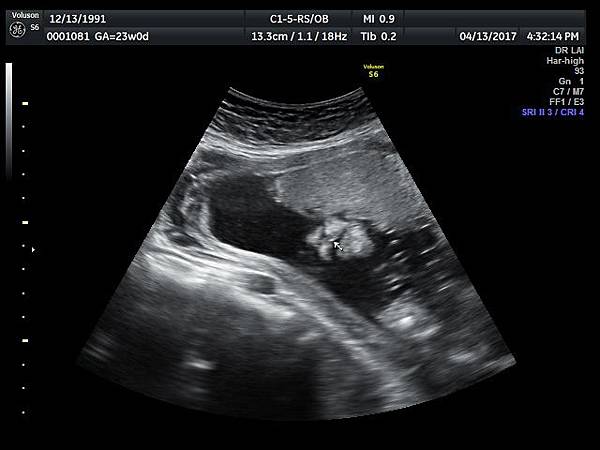

孕兒診所備忘錄 229 cleft lip and palate - I

cleft lip and palate - I